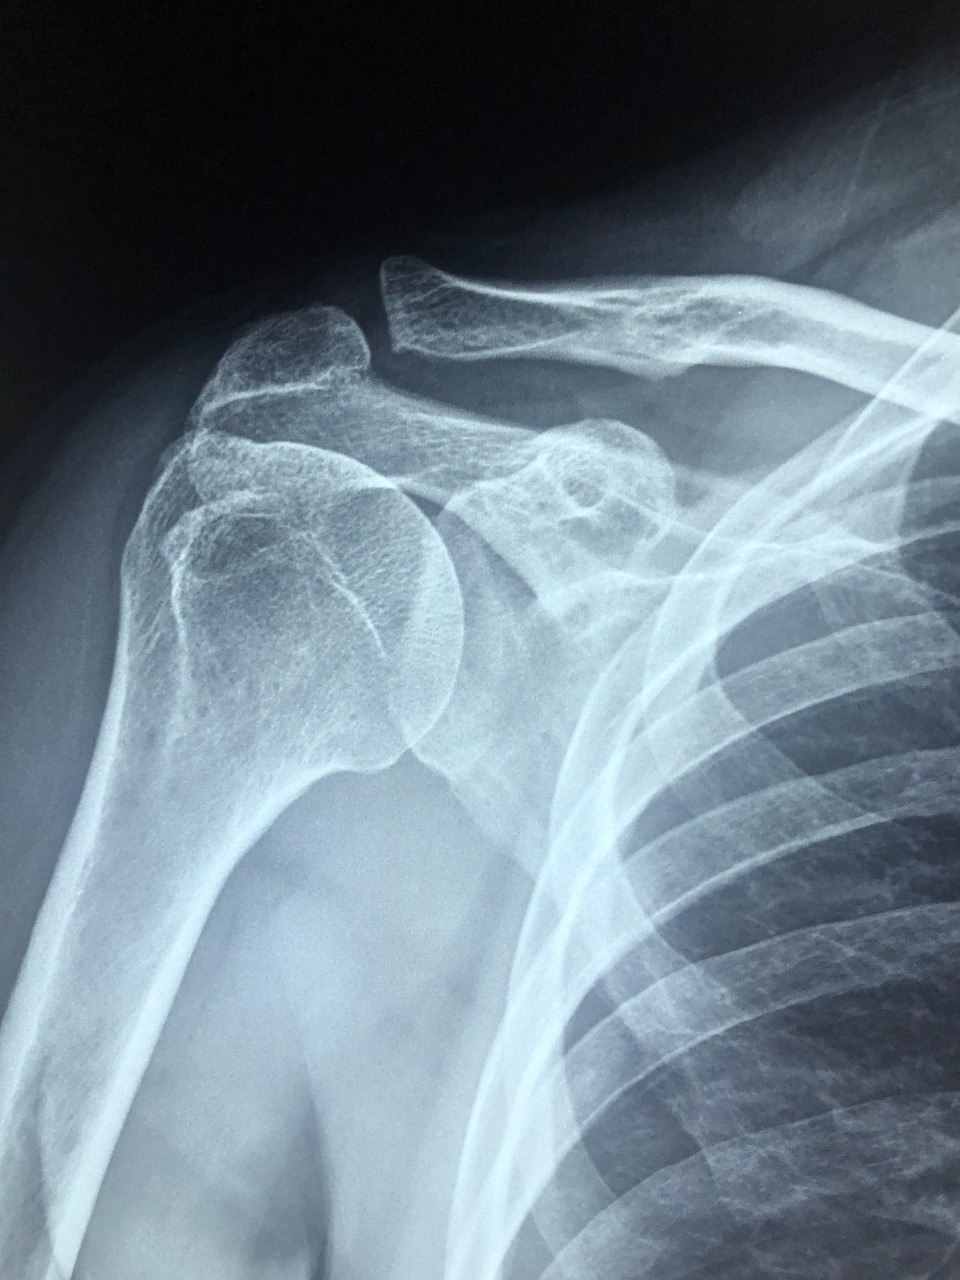

정형외과에서는 어깨 관절과 근육, 인대, 힘줄 문제를 전문적으로 진단하며, 엑스레이나 초음파, MRI 검사를 통해 원인을 파악합니다. 만약 목 디스크나 신경 압박이 의심되는 경우에는 신경외과나 재활의학과 진료가 도움이 될 수 있습니다. 통증이 일상생활에 큰 지장을 주는 경우라면 정확한 진단이 가능한 진료과를 선택하는 것이 회복에 중요한 역할을 합니다.